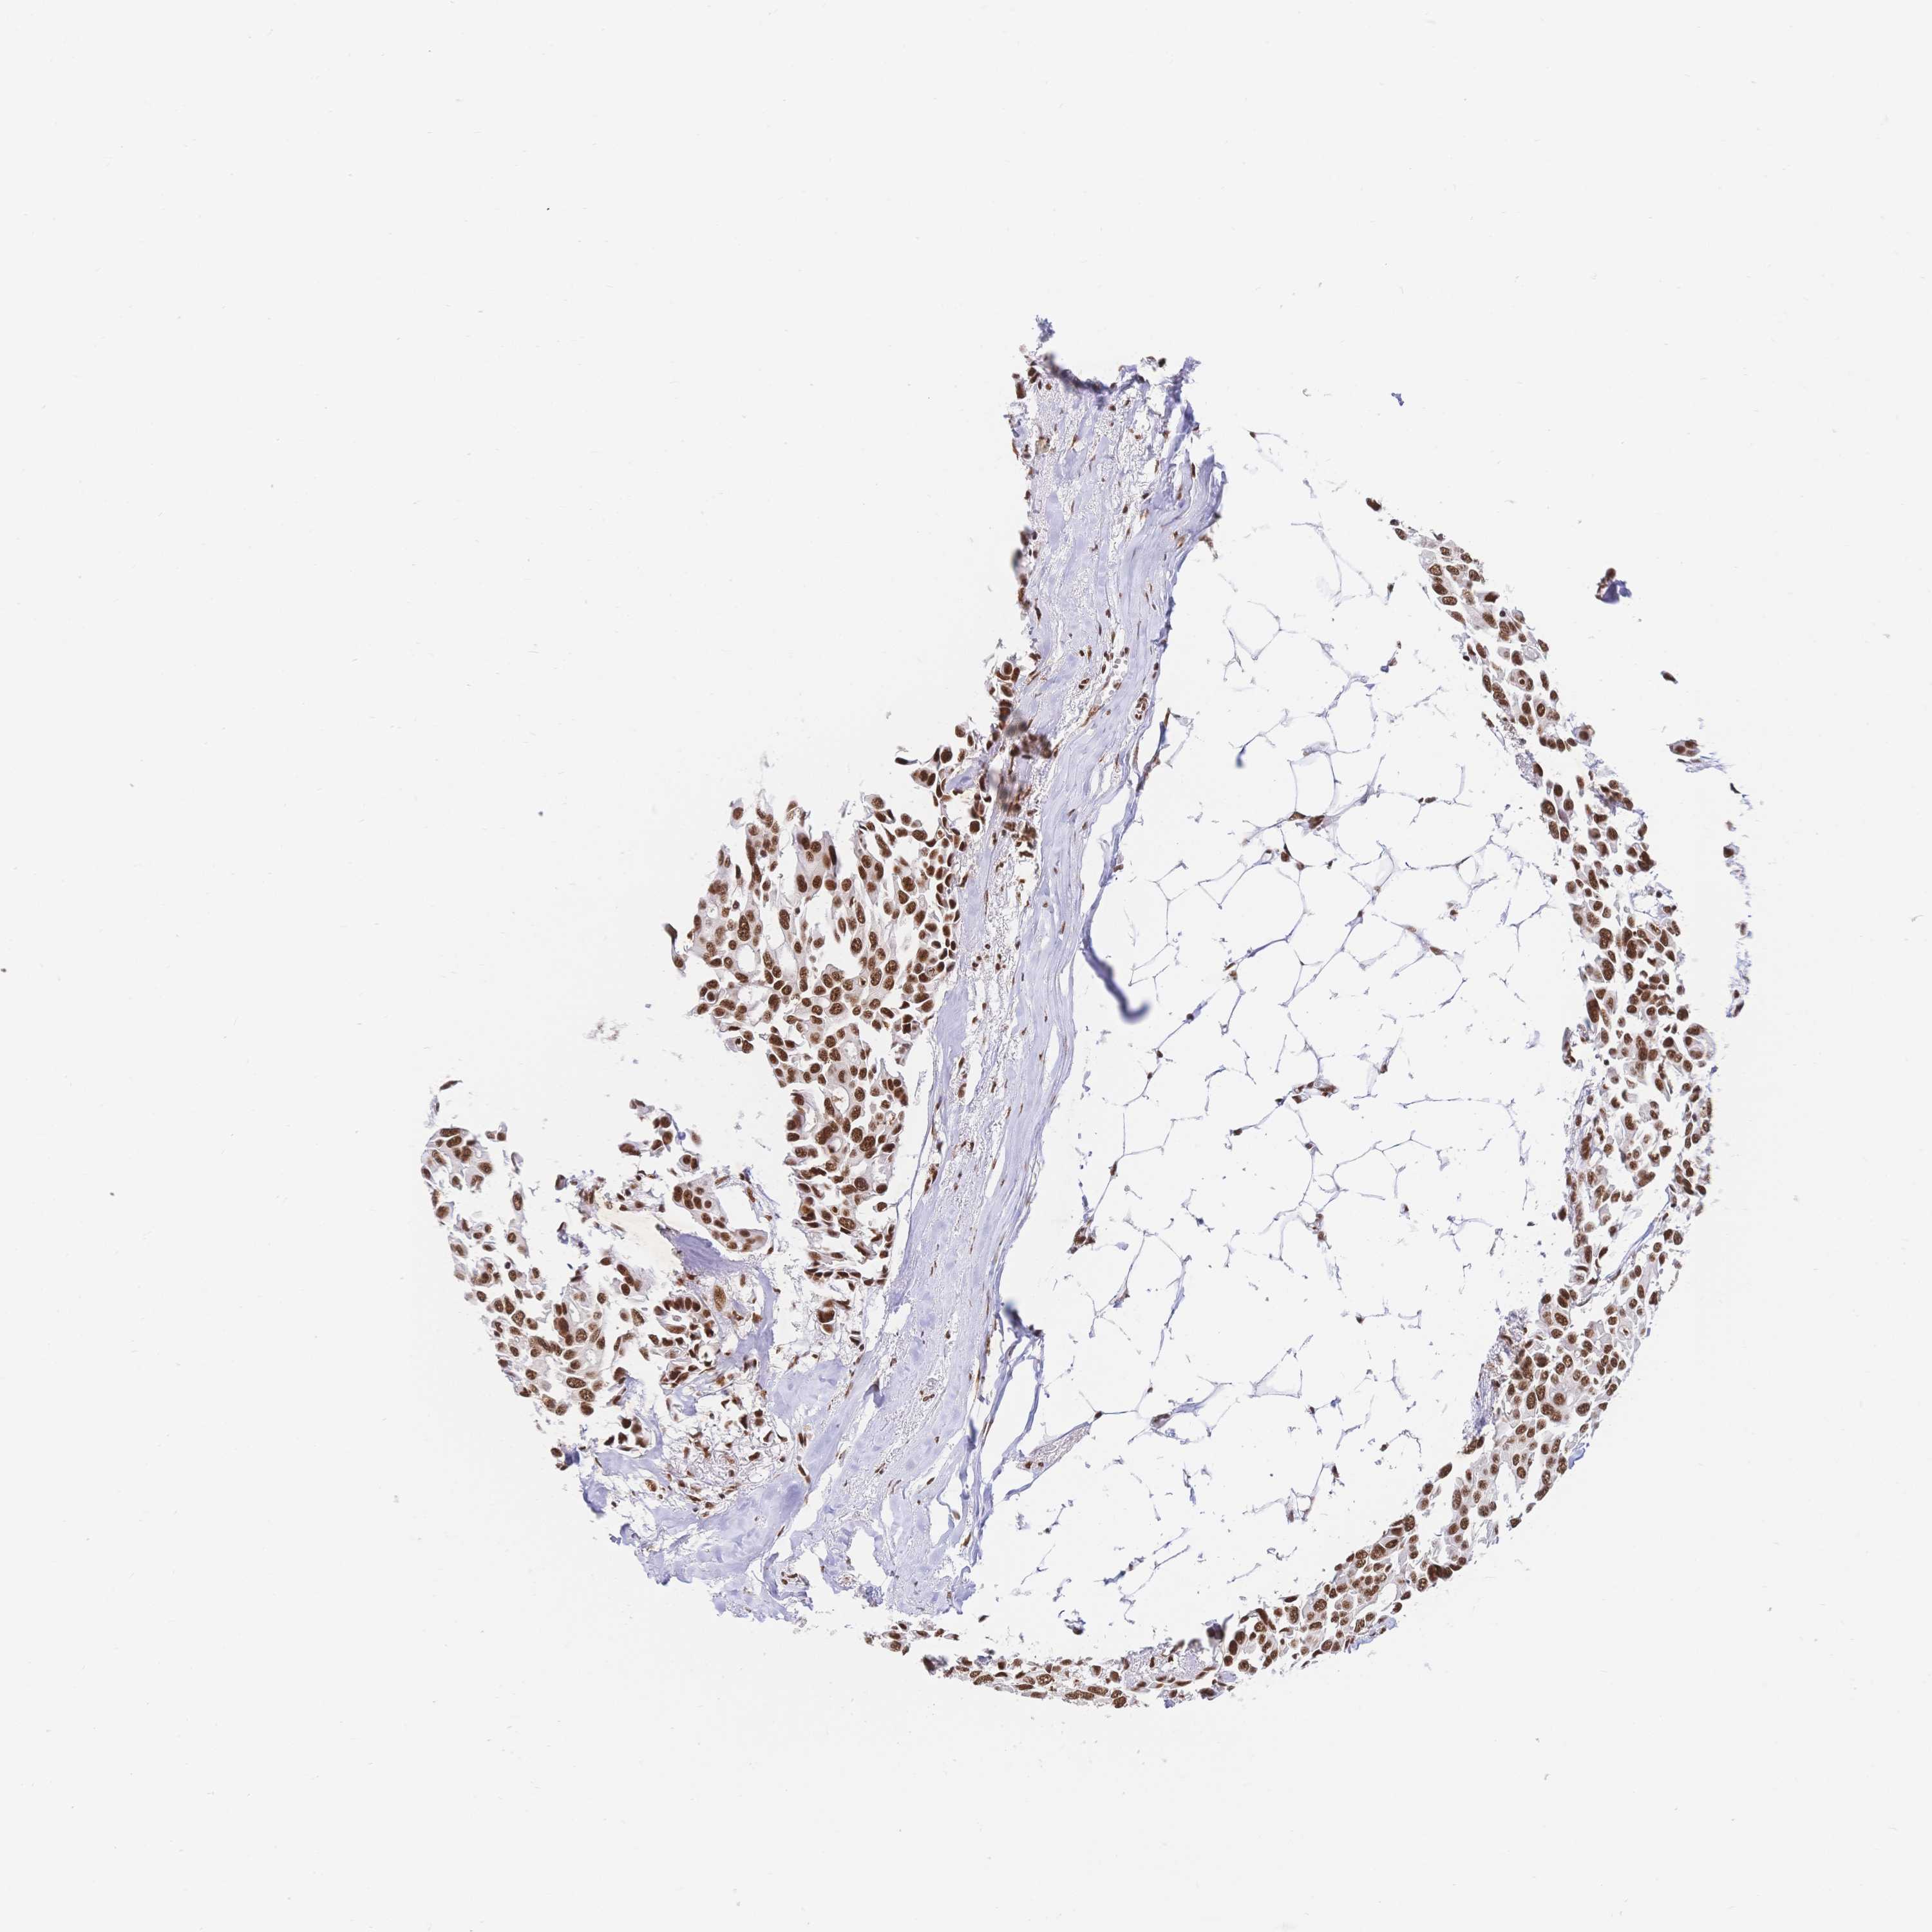

CANCER BREAST CANCER Show tissue menu

BRCA TCGA BRCA VALIDATION PROTEIN EXPRESSION